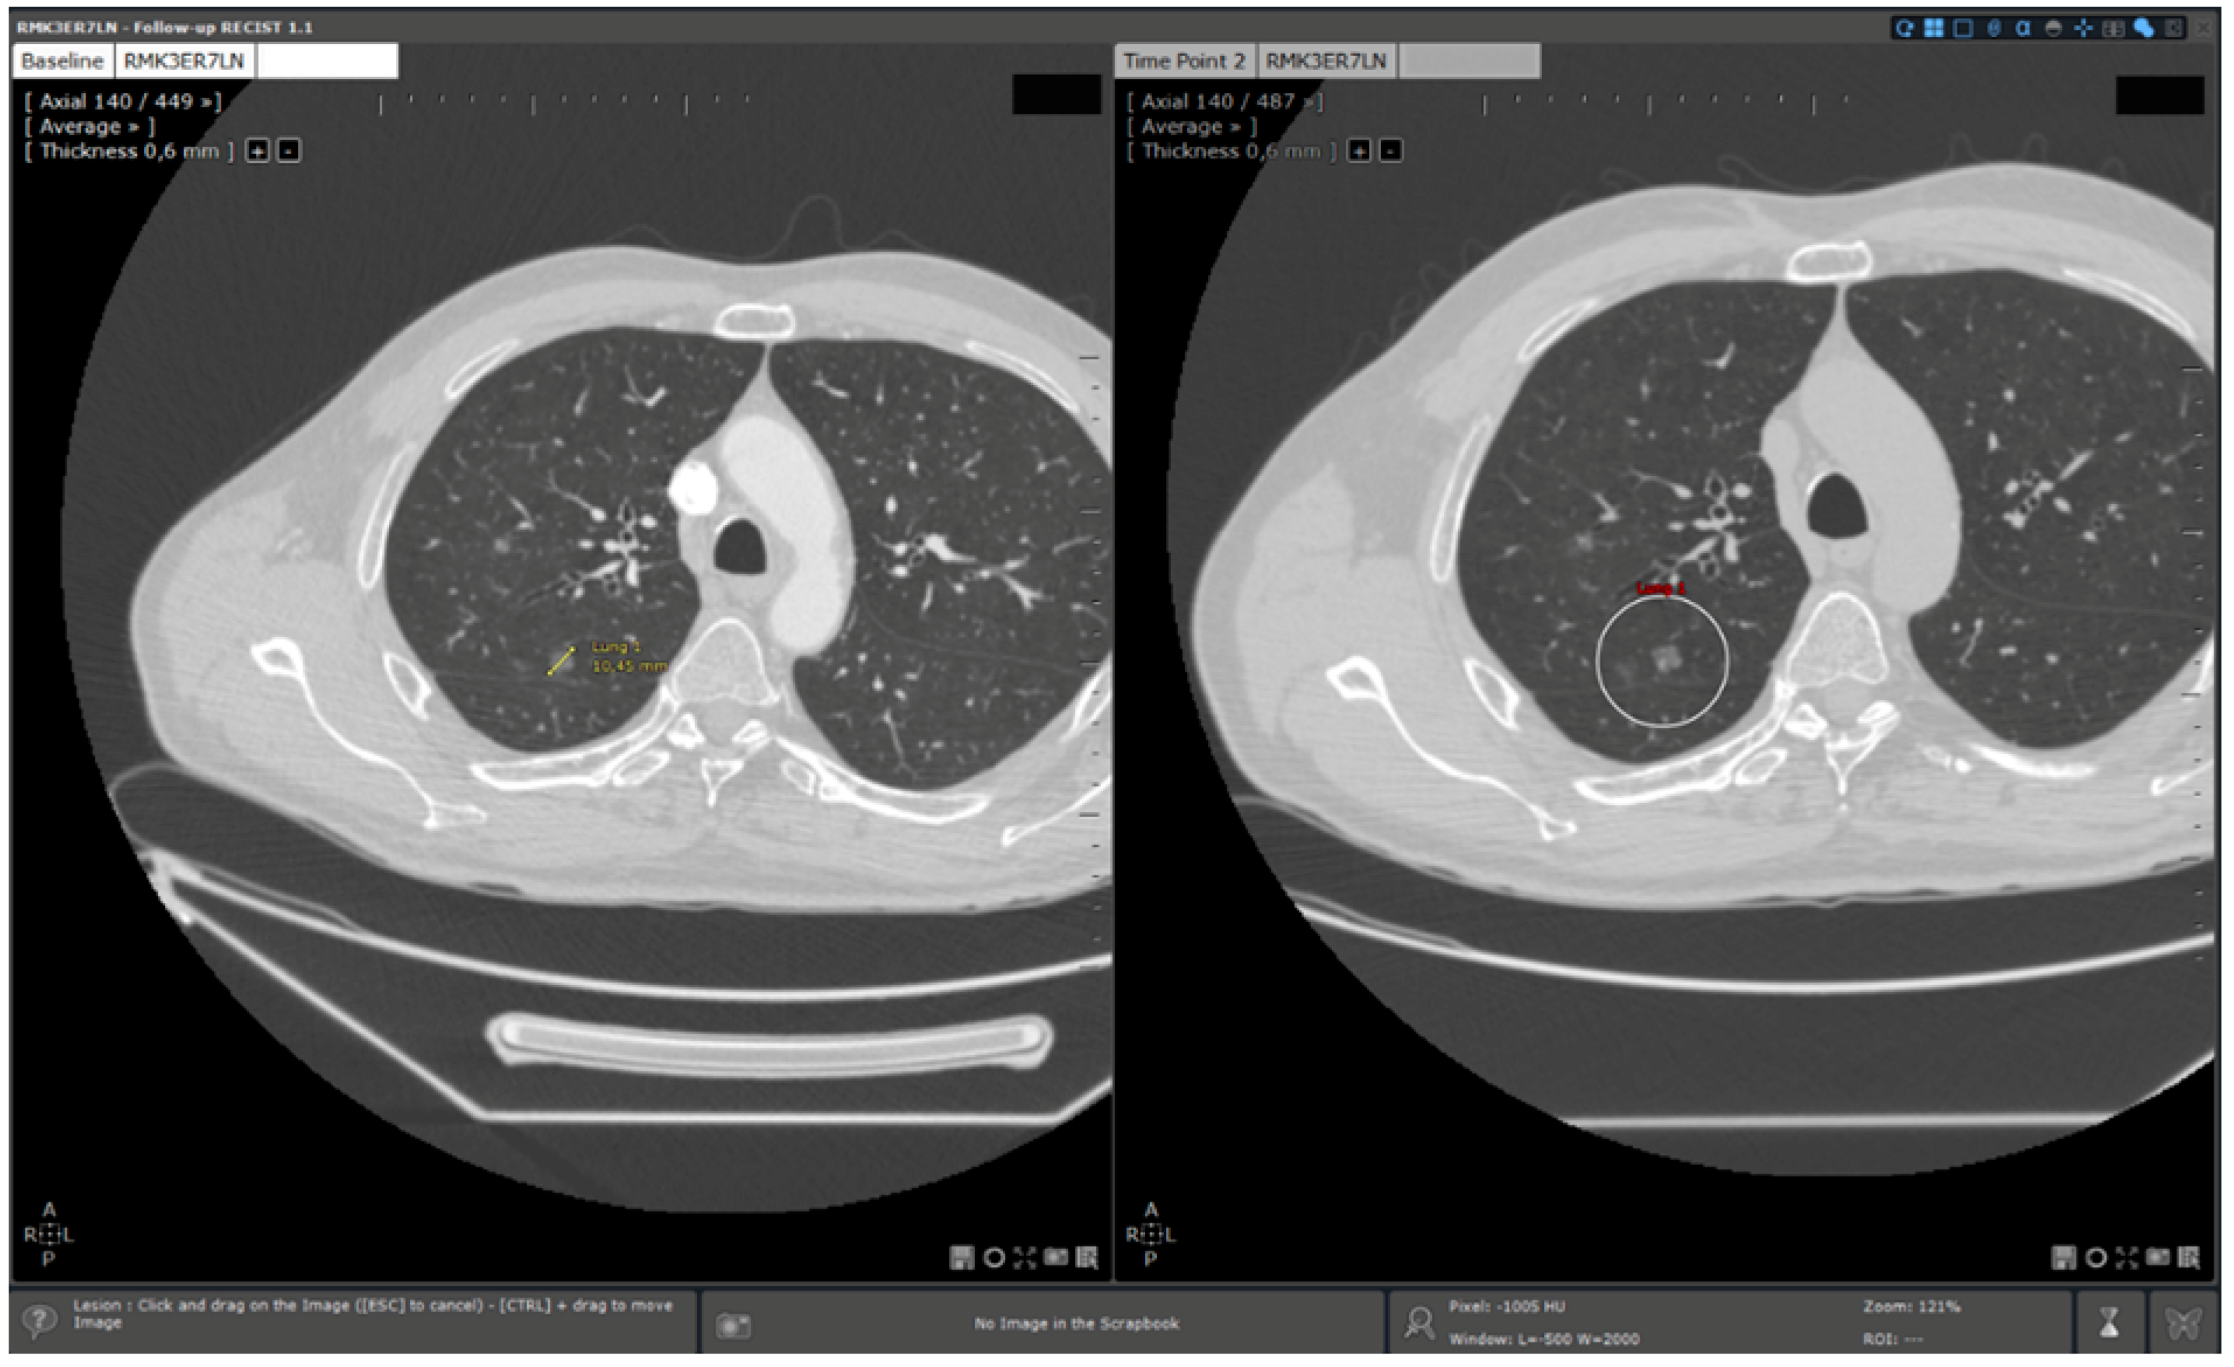

- Standard reading: Manual determination of RECIST response using a standard viewer (Myrian®, Intrasense, France) without specific options dedicated to oncologic follow ups. This reading is called “manual reading” in the rest of the article.

- Reading with dedicated software: Determination of RECIST response with the dedicated application for oncologic follow ups, Myrian® XL-Onco, with specific functionalities:

- 3D target matching technology to facilitate lesion localisation in the follow up study.

| Step 2 | Baseline study opening | Manual | Automated |

| Step 3 | Target localisation on baseline study | Manual | Automated |

| Step 4 | Target localisation on follow up study | Manual | Automated |

| Step 5 | Target measurements on follow up study | Manual | Manual |